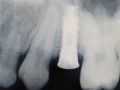

- 5.712 Implante para primeiro pré molar superior direito